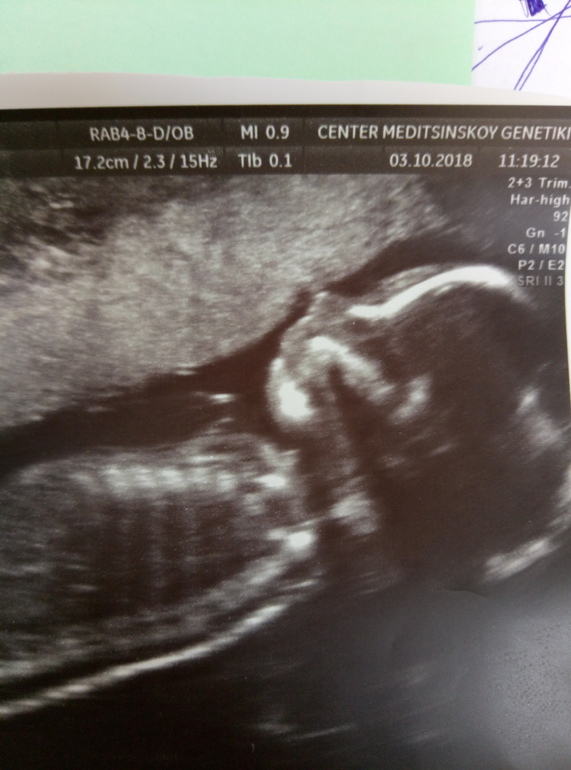

Все у нас хорошо. На той неделе ездили в генетический центр, там делали тщательное узи, посмотрели каждый орган, каждую косточку, все мне показали 😍

Малыш еще раз показался во всей красе и подтвердил что он мальчик)))

Ну и фоточка малявочки 😍